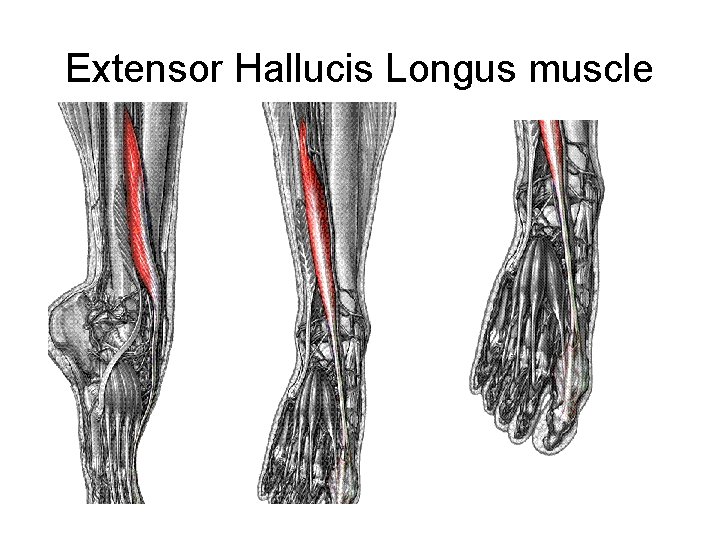

Extensor Hallucis Longus muscle

• L 5, S 1 • Extends big toe • Assists dorsiflexion of ankle • Weak ankle inversion